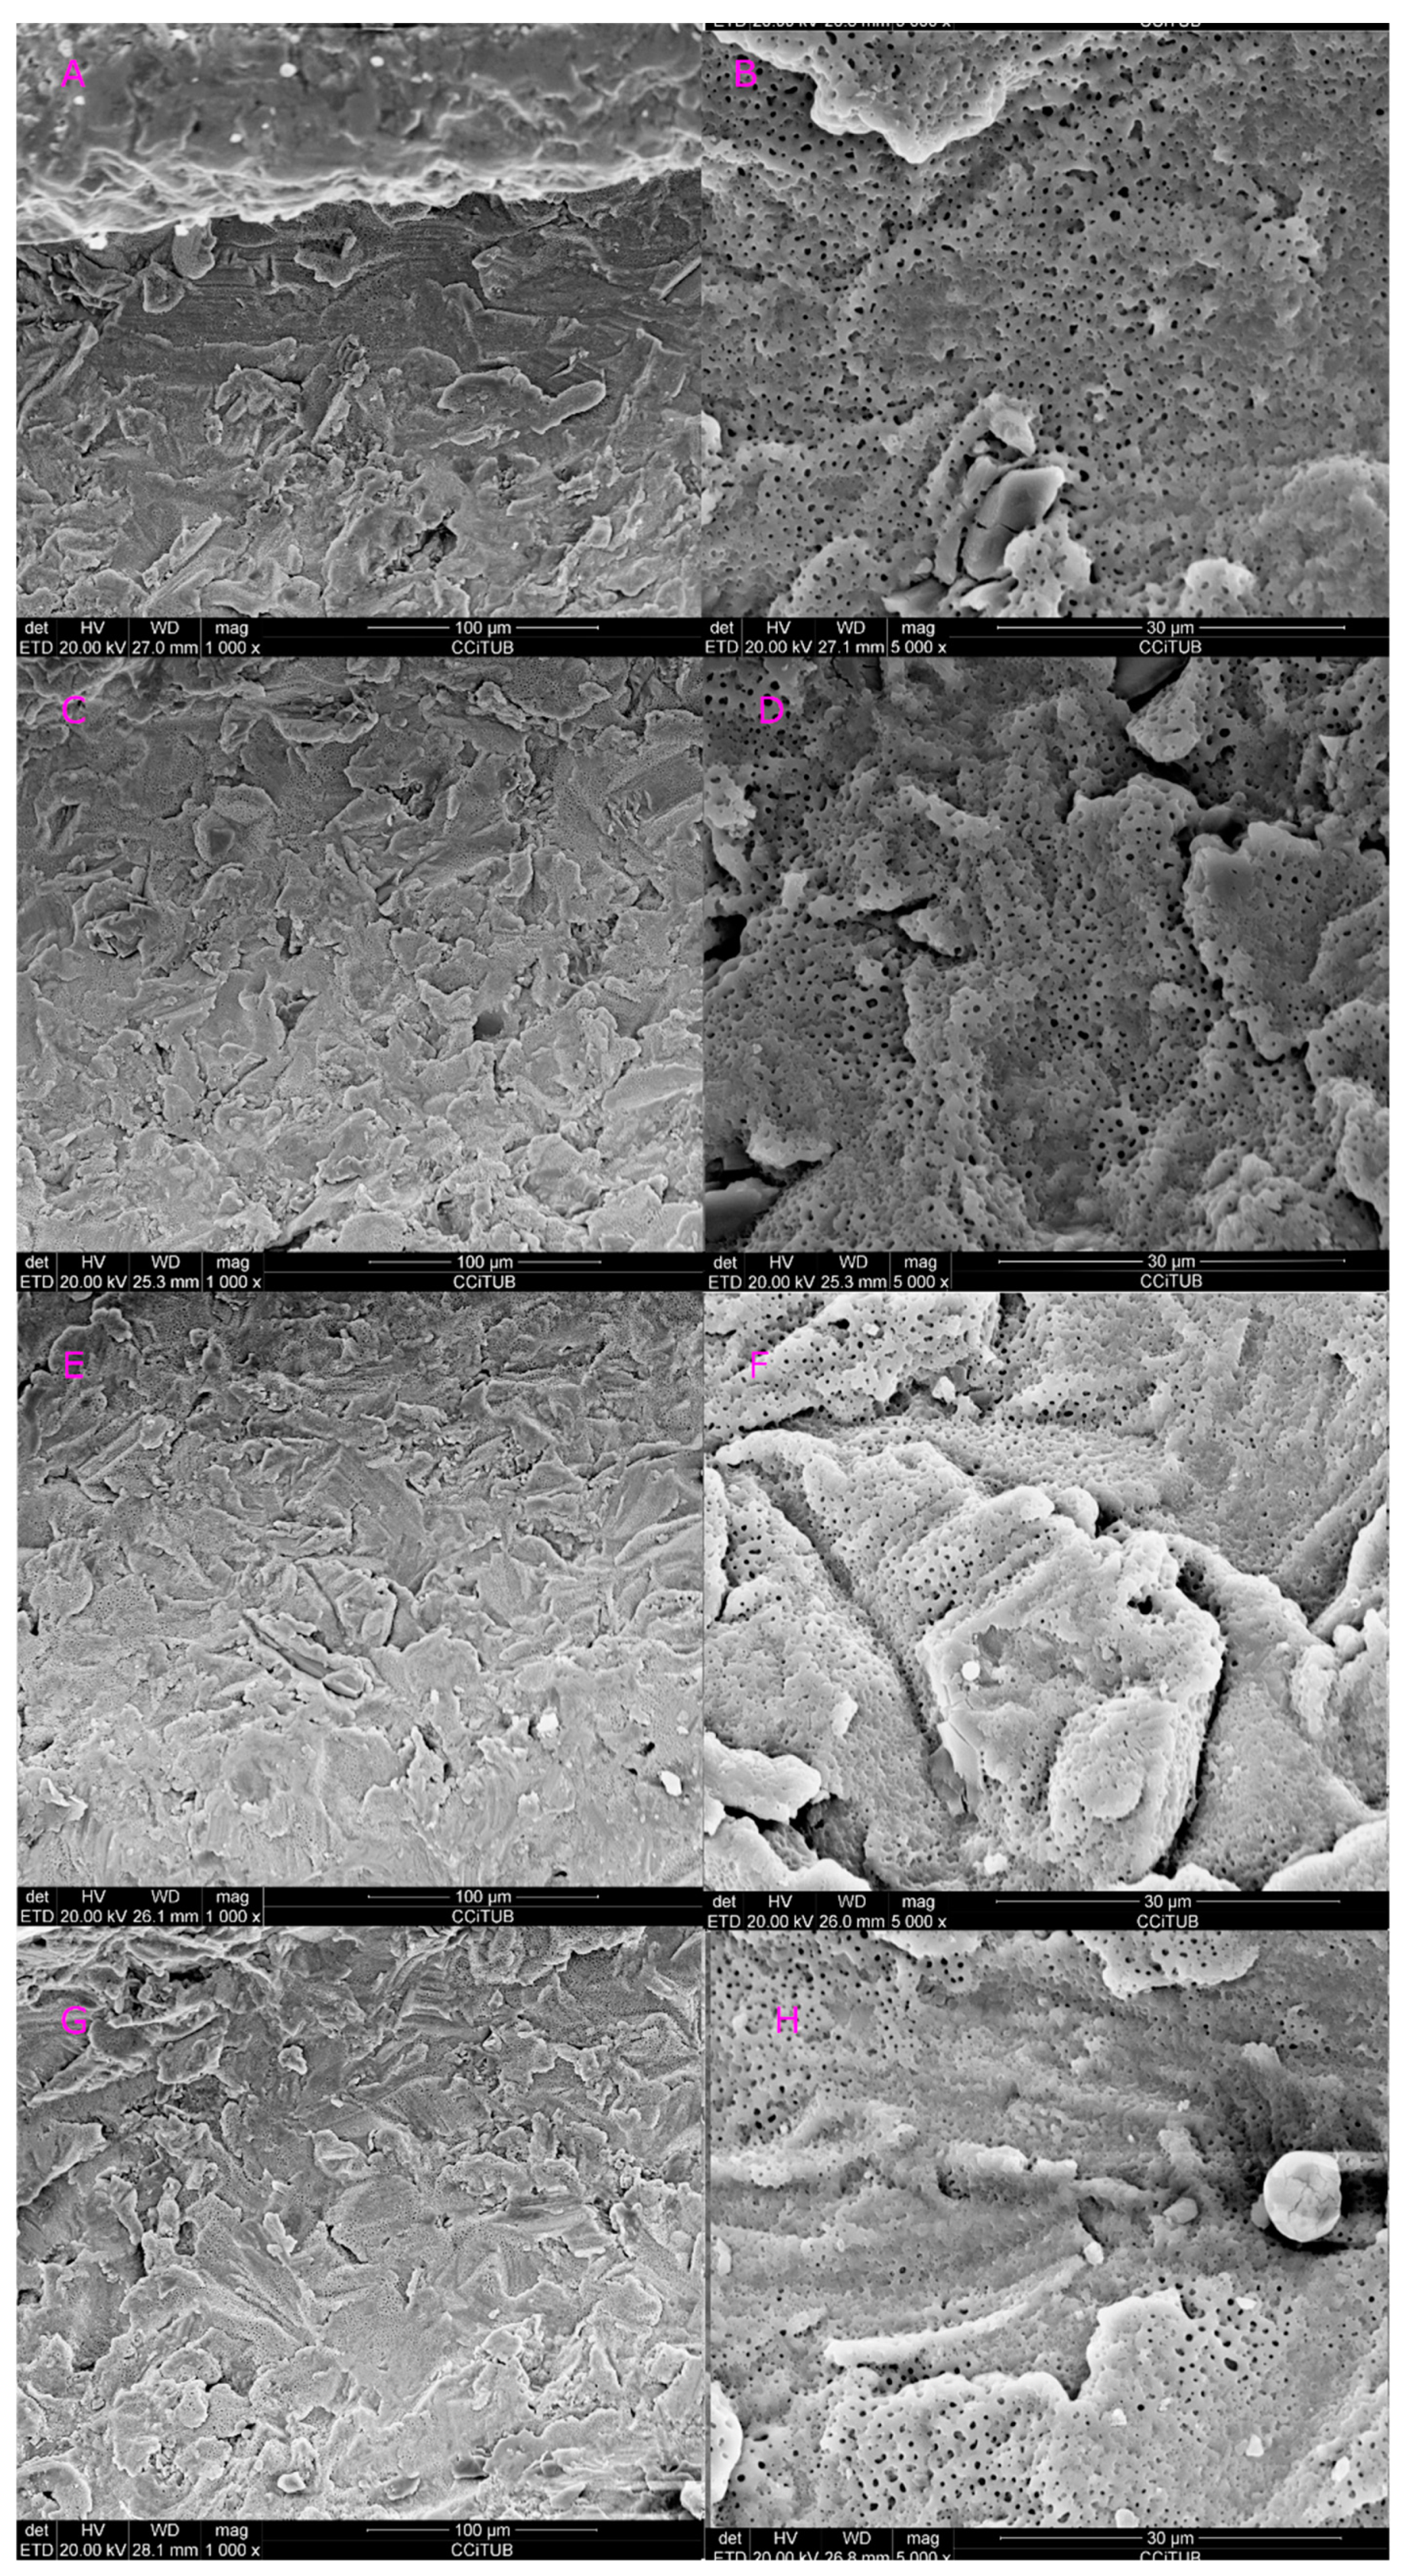

| 1.5 | 30 | 60 | Conical (415) | Class A |

| 2.5 | 30 | 60 | Conical (415) | Class C |

| 1.5 | 30 | 60 | Cylindrical (600) | Class B |

| 2.5 | 30 | 60 | Cylindrical (600) | Class B |

| 1.5 | 30 | 60 | Lateral (800) | Class A |

| 2.5 | 30 | 60 | Lateral (800) | Class B |